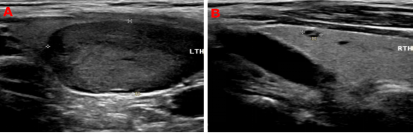

99mTc-MIBI甲状旁腺SPECT/CT融合显像图:图1+2冠状位、图3+4矢状位、图5+6横断位,提示功能亢进甲状旁腺组织(十字线交叉处)。随后的超声提示:双侧甲状旁腺区多断面超声扫查未见明显异常占位性病变;双侧甲状腺结节,其中左侧叶内一枚33mm×19mm低回声、边缘光滑、内无强回声结节。颈部B超图:A、B(纵切面)分别显示甲状腺左叶、甲状腺右叶;左叶内一低回声结节。

临床资料和核医学检查高度怀疑患者存在原发性甲状旁腺腺瘤,但超声检查尚不支持。为此,老年科吕荣主任医师团队、核医学科尤徐阳主任医师团队、介入科徐斌主任医师团队进行了多学科MDT讨论,认为:患者甲状旁腺功能亢进症诊断明确,高度可疑甲状旁腺腺瘤病灶可能起源于少见的甲状腺内异位甲状旁腺组织,或者是因为甲状旁腺腺瘤组织向上生长推移到甲状腺内;该病灶包膜完整,边界清晰,颈部未见明显肿大淋巴结,排除为恶性病变;患者年老体弱,合并多种疾病,可采取超声引导下可疑病灶组织穿刺证实,可疑病灶一旦确定为甲状旁腺来源,可立即行超声引导下病灶消融术。患者及家属对当前及下一步诊疗方案满意,希望能够通过微创治疗方案解除痛苦。